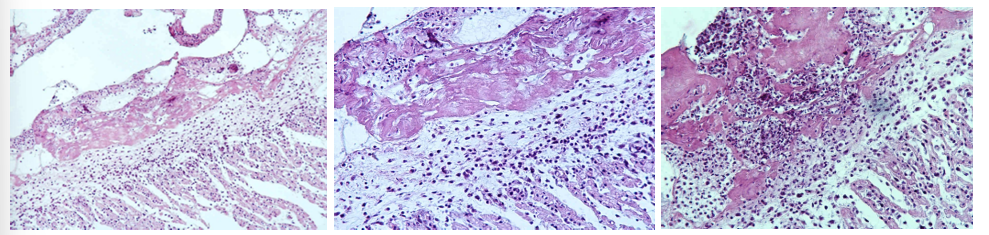

this is?

Cirrhosis hepatis (Hepatitis interstitialis chronica)

Description: Proliferated fibrinous tissue found in the whole section. It is infiltrated by chronic inflammatory cells (lymphocytes, plasma cells, macrophages). Fibrinous tissue originates from interlobular spaces and spreads into the center of the lobules, causing press atrophy of liver parenchyma. Regeneration of bile ducts can be seen in new fibrinous tissue.

Etiology: End-result of necrosis or apoptosis and active inflammation with chronic fibrosis.

Pathogenesis: End-stage diffuse hepatic disease characterized by nodular regeneration with fibrovascular bridging scars containing shunts. Regeneration of tissue leads to formation of variable sized nodules between fibrous connective tissue, distorting the entire liver. In the end, the liver is unable to perform its normal function, and cirrhosis can lead to ascites and hypoproteinemia.

Actinomycosis

Description: We can see actinomycotic nodules. In the center there are bacterial colonies consisting of intertwined radiating filaments (rays), capped by eosinophilic hyaline material (clubs), creating a sunburst pattern- sulphur granules, surrounded by disintegrated neutrophils- pus. An outer area of large mononuclear cells with abundant, often foamy cytoplasm- histiocytes and plasma cells, surround neutrophils. Non-specific granulation tissue border nodules.

Etiology: Caused by Actinomyces bovis

Pathogenesis: Hard, irregular, enlargement result from infection of mandible or maxilla, leading to the disease of lumpy jaw.